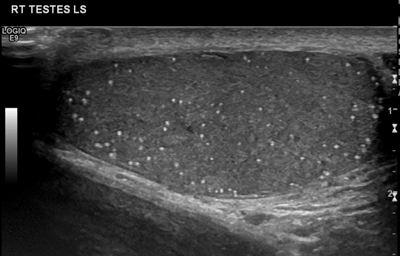

Testicular microlithiasis is most commonly diagnosed by ultrasound, as the microliths are clearly identified as hyperechoic foci which do not demonstrate posterior acoustic shadowing, less than 3mm in size. Different definitions exist about the diagnosis of microlithiasis, but the most universally accepted definition is that five of more microliths are seen per field of view on ultrasound (Figure 3). When testicular microlithiasis is widespread and seen throughout the testis, it is described as a ‘snow-storm’ appearance [4].

Figure 3: Longitudinal section of the right testis showing microlithiasis,

with more than five microliths seen in the field of view.